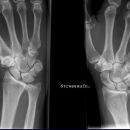

Scaphoid-Quartett

Dringender Verdacht auf Scaphoidfraktur (2) bei zweifelhaften Befund in den Standardprojektionen.Notwendigkeit fraglich, da bei klinischen Verdacht und zweifelhaften Röntgenbefund in den Standardaufnahmen des Handgelenks ohnehin die Ruhigstellung indiziert ist, so dass sich eine weiterführende Diagnostik zunächst erübrigt. Ist auch die Kontrolluntersuchung nicht eindeutig, so sind CT oder Szintigraphie in ihrer Aussage zuverlässiger als die Spezialprojektionen.

Scaphoidfrakturen: 70% der Frakturen der Handwurzel sind Scaphoidfrakturen. 2/3 sind im mittleren Drittel. Meist Querfrakturen.

Dehizenz > 1mm -> instabil -> Gefahr Pseudarthrose.

Cave: Begleitverletzungen: Proc. syloideus radii, Lunatum, Capitatum, SL-Dissoziation, perilunäre Dissoziaton, DeQuervain Luxationsfraktur.